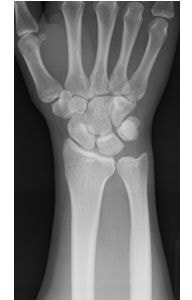

TFCC損傷の原因となる尺骨突き上げ症候群とは。